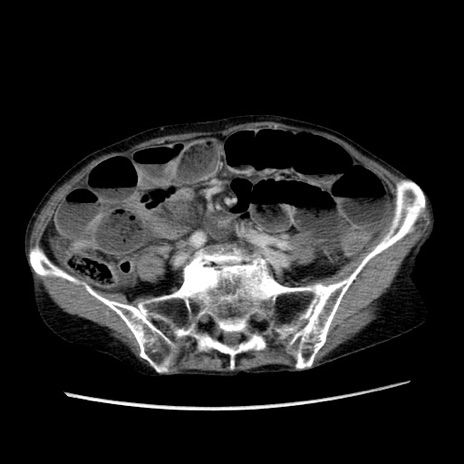

冠状断像